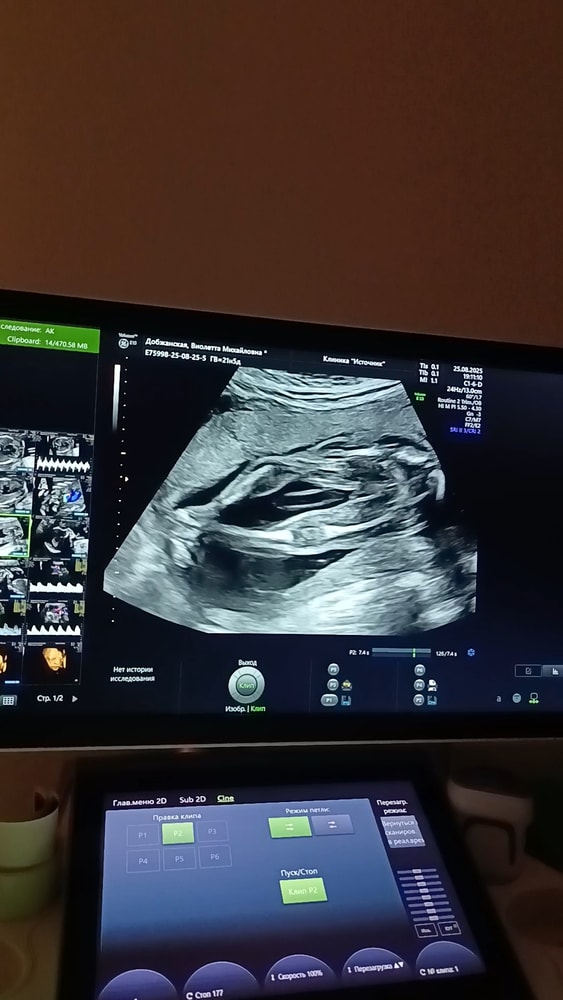

Добрый день! Подскажите пожалуйста, до 21 недели несколько врачей по узи видели мальчика, а на 23 сказали, что девочка🥹. Есть такие снимки с узи 21 недели (ножки, вид снизу), можно ли определить пол? 😅 Мне почему-то, кажется, что это всё-таки девочка, между ножек ничего нет🙈

Ну, по второму снимку я бы подумала что мальчик. Но т.к. срок уже большой, сложно поверить, что врач ошибается. Хотя и такие истории бывают). Рекомендация - пройдите еще одно УЗИ и пусть вам прямо на экране в реальном времени покажут, не на снимке)

По второму снимку на мальчика похоже. Вообще по такому снимку это мы не очень видим, а врач должен хорошо видеть.